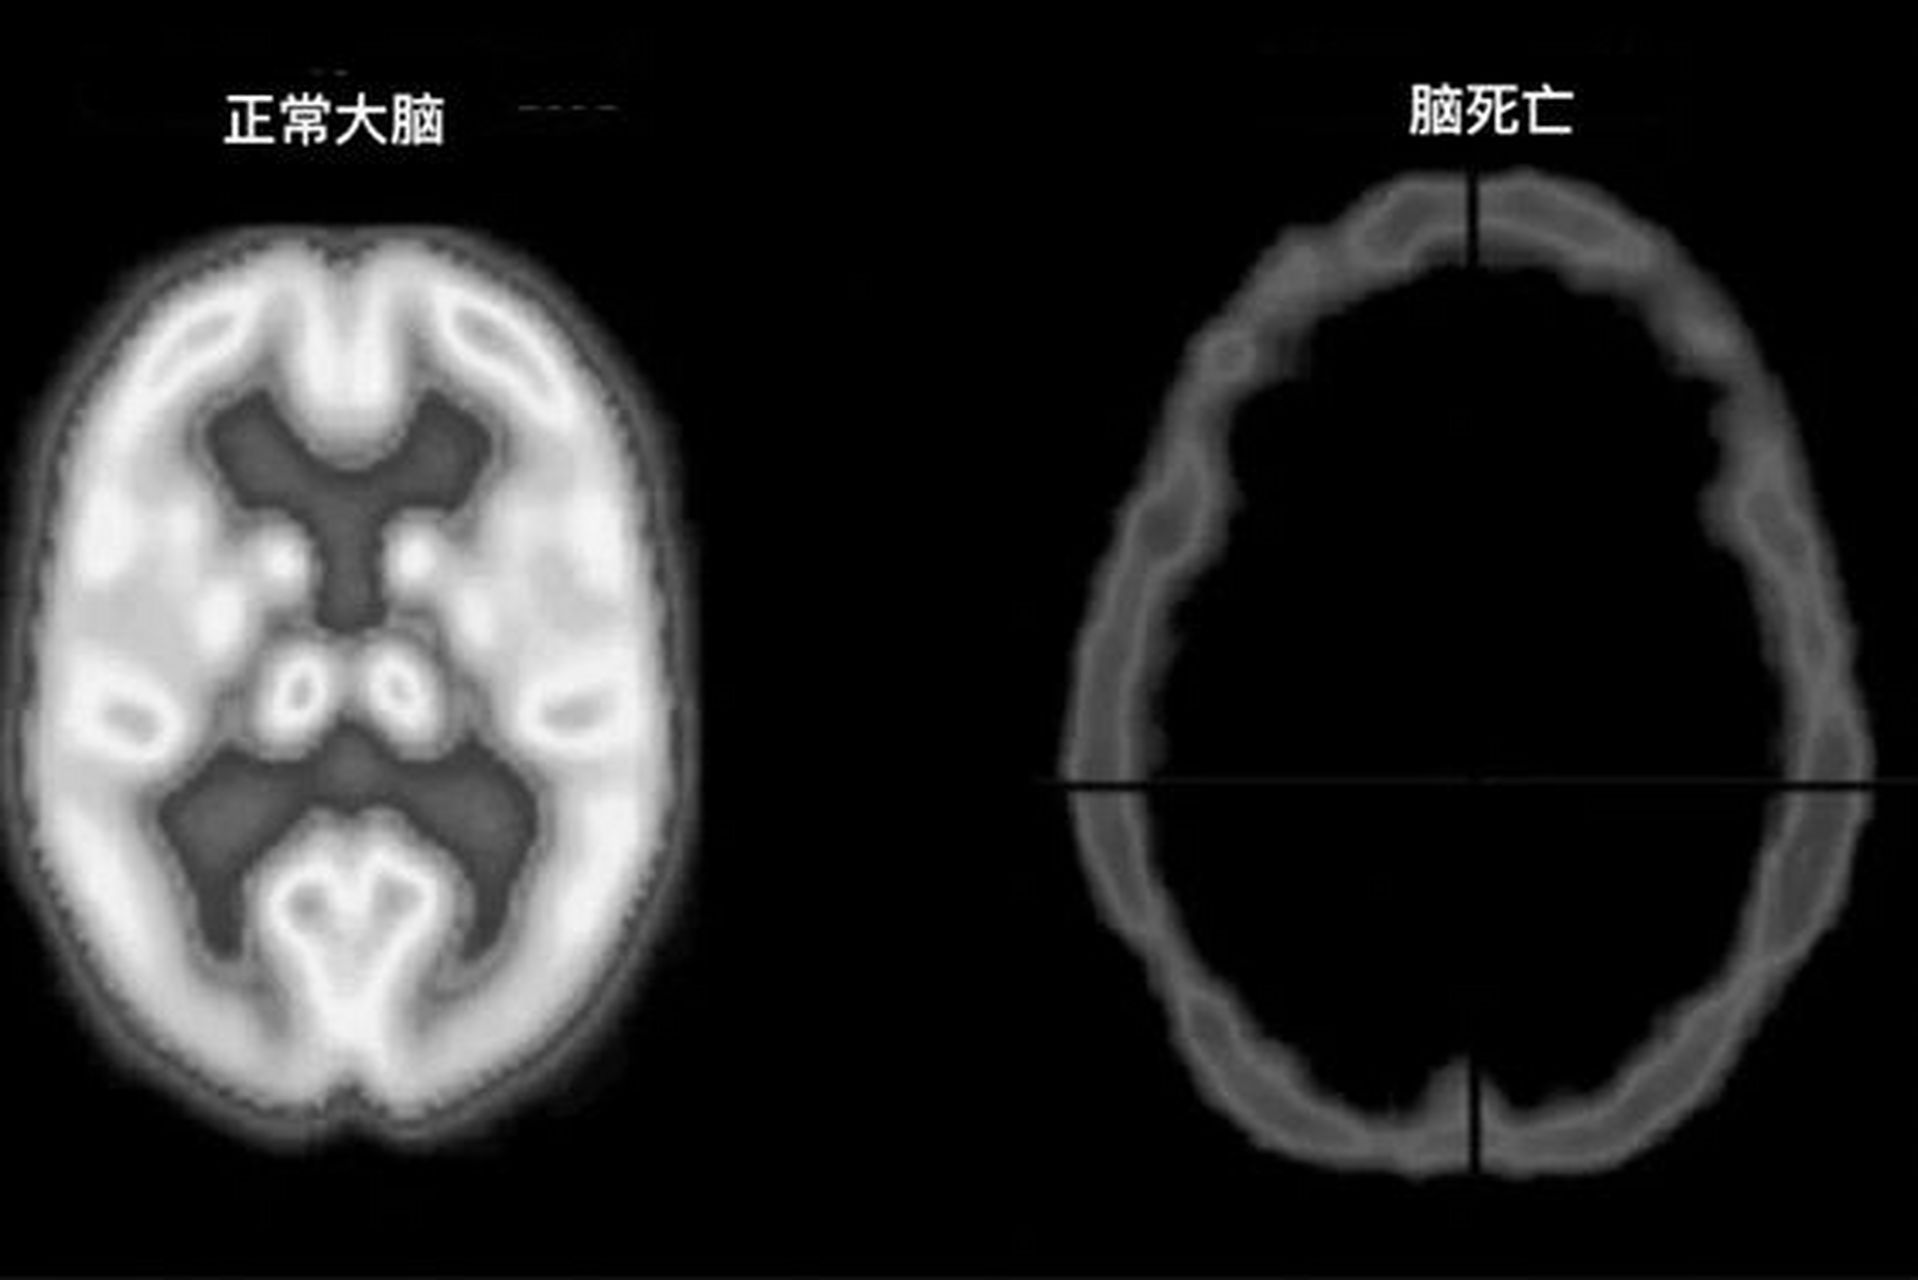

正常大脑与脑死亡 脑死亡是指永久性丧失脑部活动. 因此,患者无法自主